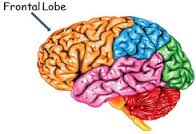

Brain Anatomy

To fully understand what happens to an injured brain, it is important to know the basic anatomy and function of a healthy brain. The brain is safely enclosed inside the protective covering of the skull. A brain is made of nerve cells (neurons) that form routing pathways that run throughout the brain and body. The function of these pathways or tracts is to deliver messages like breathing; regulating body temperature, heart rate, metabolic activities, and controlling behavior, personality, thoughts, and the five senses of smell, touch, vision, taste and hearing. The brain is made up of six parts.

- Frontal lobes

- Temporal lobes

- Parietal lobes

- Occipital lobes

- Brain stem

- Cerebellum

Frontal Lobes

This part of the brain is responsible for behavioral output (social and cognitive behaviors), as well as body movement. Some of the many behaviors and functions of the human brain include: inhibition; behavior initiation and self-regulation; abstract reasoning; attention and working memory; executive functioning (multitasking, organizing, etc.); and movement (muscles involved in speech, facial expressions, etc.).This brain region is often affected by TBI from motor vehicle accidents, especially injuries caused by rapid acceleration-deceleration type events.

This part of the brain is responsible for behavioral output (social and cognitive behaviors), as well as body movement. Some of the many behaviors and functions of the human brain include: inhibition; behavior initiation and self-regulation; abstract reasoning; attention and working memory; executive functioning (multitasking, organizing, etc.); and movement (muscles involved in speech, facial expressions, etc.).This brain region is often affected by TBI from motor vehicle accidents, especially injuries caused by rapid acceleration-deceleration type events.